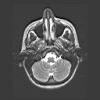

Schedel